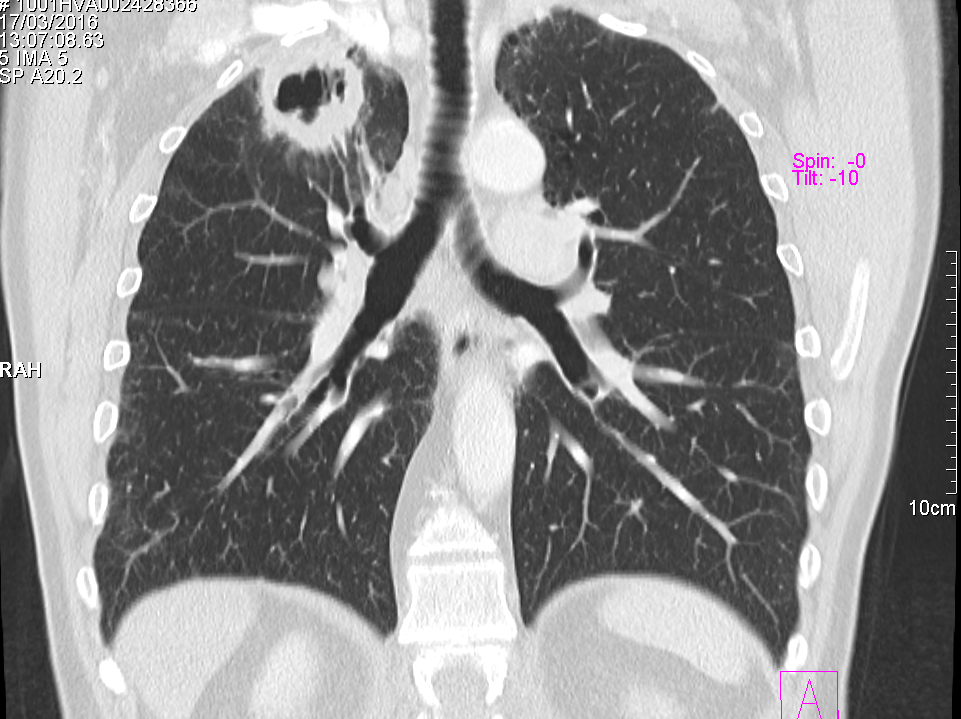

Obtenemos las siguientes imágenes en distintos planos:

Vemos que la estructura cavitada posee una pared muy gruesa, más típica de un proceso neoplásico, y una cavidad hipodensa. Confirmamos su localización en el lóbulo superior derecho y anterior. Descartamos proximidad a vasos y estructuras mediastinicas, así como invasión de la pared torácica. Y lo mas importante es que apreciamos que el bronquio principal mas proximal a la masa cavitada, el bronquio anterior del lóbulo superior derecho, se encuentra amputado cuando llega a la masa y no comunica con la cavidad del interior de la masa,